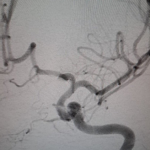

One of the key components of our stroke center is the Neuroangiography biplane suite. This advanced imaging system enables precise diagnosis and treatment of stroke and brain aneurysms. However, the cost of this technology is substantial, with a single biplane suite costing millions of dollars. Your support will directly contribute to acquiring this life-saving technology and ensuring better stroke treatment for thousands.

We provide devices and treatment of complex brain aneurysms and vascular malformations free of cost. These are some of the complex brain aneurysm we have recently treated in Pakistan. Devices and catheters used for all procedures were provided by Pakistan Stroke Initiative, and in some cases charges for hospitalization as well.